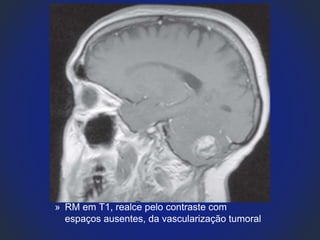

» RM em T1, realce pelo contraste com

espaços ausentes, da vascularização tumoral